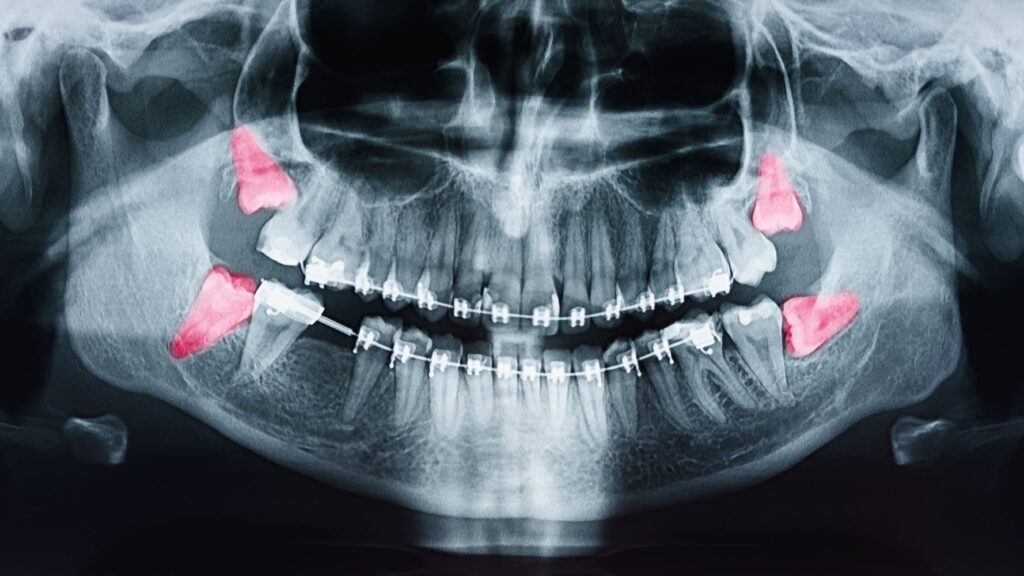

Một người trưởng thành thông thường có 4 chiếc răng khôn, 2 răng ở phía trên và 2 răng ở phía dưới. Răng khôn sẽ mọc sau 28 chiếc răng và ở vị trí cuối cùng trong hàm. Nếu không đủ chỗ để mọc, răng số 8 này sẽ tự tìm vị trí hoặc hướng để mọc lên.

Nếu không mọc bình thường, răng số 8 sẽ mọc ngược hướng xương hàm, đâm thẳng vào răng hàm lớn thứ 2. Khi đã mọc lên được khỏi lợi sẽ không mọc nữa và ngừng phát triển vĩnh viễn.